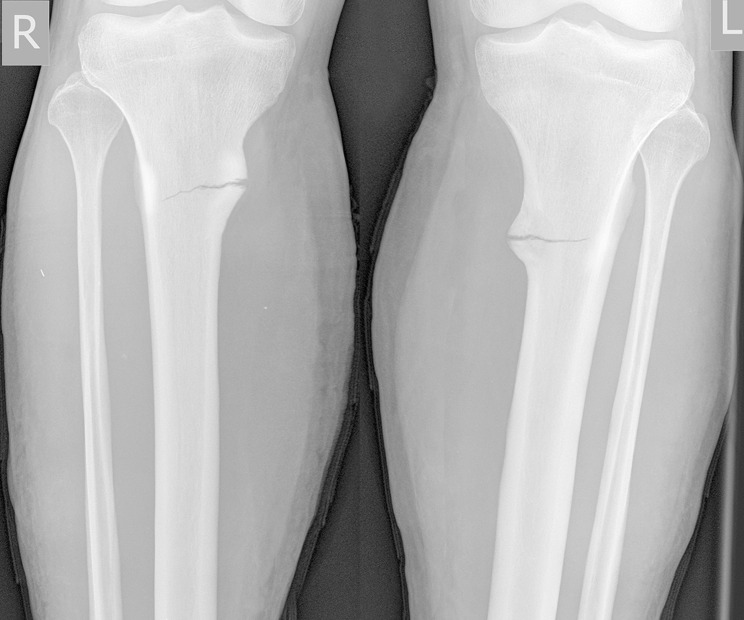

Aim: To familiarize specialists with the possibility of simultaneous bilateral stress fractures of amputation residual limbs resulting from intensive loads and poor-quality prosthetics causing chronic compartment syndrome. A case of bilateral stress fractures of the tibia in a 28-year-old male military serviceman with paired transtibial amputation is presented. The fractures occurred in the process of active exploration of poorly fitting prostheses, complicated by chronic compartment syndrome that masked the clinical picture.

Techniques: Radiography, ultrasound, blood biochemistry, measurement of subfascial pressure.

Conclusion: With complaints from the patient with an amputation stump of muscle and bone pain that appeared after exercise, passed after rest, and reparative reaction detected on radiographs, functional overstrain of the bone should be suspected, which can potentially lead to a stress fracture. The causes of stress fractures in the patient were acute overstrain of the bone tissue during prosthesis development, noncompliance with the loading and resting regimes, and local disturbance of the bone blood supply due to the narrowed rigid socket of the prosthesis. Stress fractures of the bone tissue of the amputation stump contain elements of insufficiency and fatigue. Chronic compartment syndrome may exacerbate and mask the stress fracture.